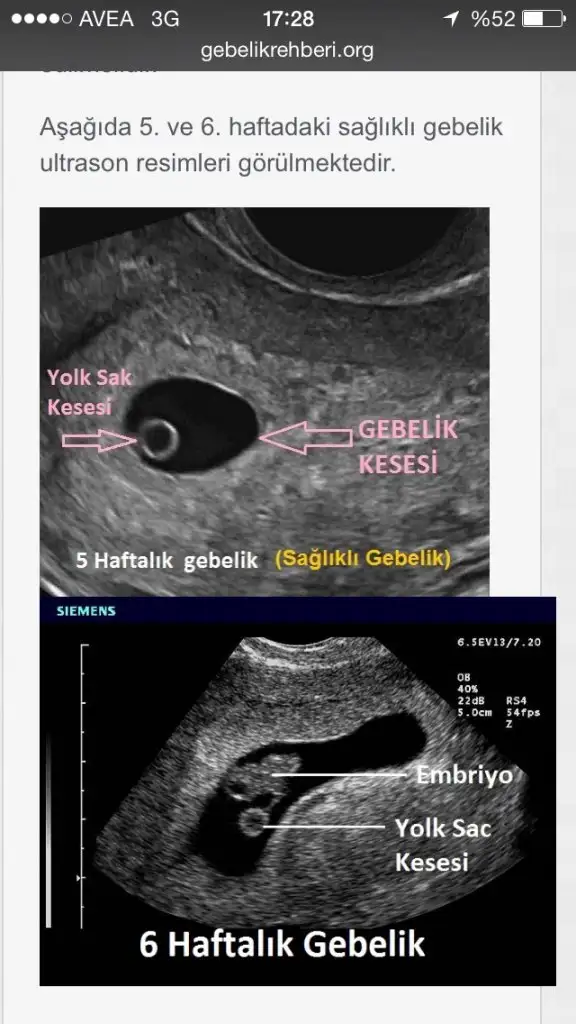

yolk sac nedir ya? Geçen seferCnm boş gebelik değil çok şükür o gördüğü kese değilmiş kanama alanı imiş kese sanmış daha sonra Değerler arttı ve küçük bir kese görüldü yolk sac da var ama bebek görmek için küçük henüz.kanama alanı hala duruyor kahverengi leke gelebilir Endişe etme düşük riski var dedi ama korkma dedi ilaçlar iğneler verdi.haftaya Salı yada Çarşamba kalp atışları için gideceğim inşallah herşey yolunda gider wc ye korkarak gidiyorum

Bu bebeği besleyen kısımmış cnm o yoksa bebek hiç yok demektir yani boş gebelik olma riski çok fazlayolk sac nedir ya? Geçen seferDESIGNER27 de yazmıştı yanlış yazdığını düşünmüştüm.bilmediğimiz ne çok şey var yahu...

Allahım kese yi tekrar görmeyi nasip etsin bizlerede canım ya...Bu bebeği besleyen kısımmış cnm o yoksa bebek hiç yok demektir yani boş gebelik olma riski çok fazla